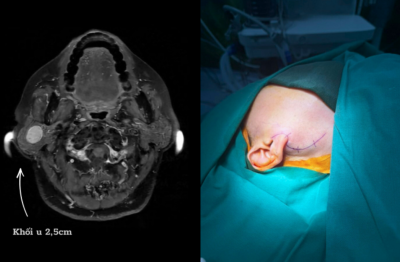

Bệnh viện Đa khoa Hồng Ngọc tiên phong ứng dụng công nghệ C-arm 3D thế hệ mới trong phẫu thuật chấn thương chỉnh...

DNTH: Giờ đây, phẫu thuật viên có thể dễ dàng xác định nhanh vị trí tổn thương, can thiệp chính xác chỉ với 1 lần quét dưới máy C-arm 3D tích hợp trí tuệ nhân tạo AI. Nhờ đó, rút ngắn thời gian mổ, giảm nguy cơ biến chứng, đẩy...